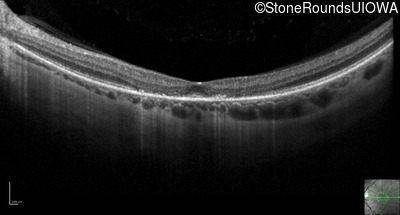

Optical Coherence Tomography - Left - 20/250

Exemplar / OCT Stack